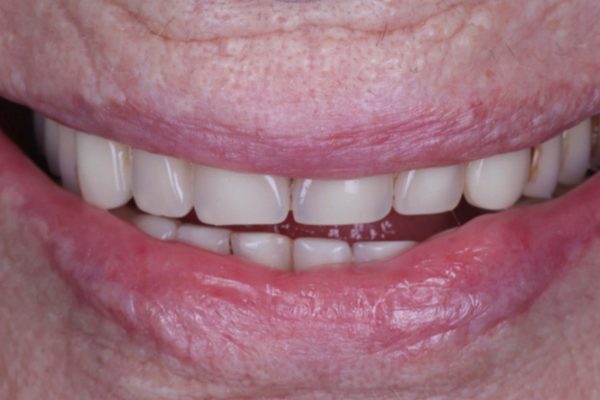

Figures 1-3 show a 90-year-old patient, who presented with a fractured 26-year-old implant bridge. This bridge has been in place for 24 years without incident. The patient was very happy with it.

The occlusion and aesthetics were checked, and the patient was delighted that we’d managed to refurbish the bridge and achieved her goals. The final result is shown in Figures 7-11.